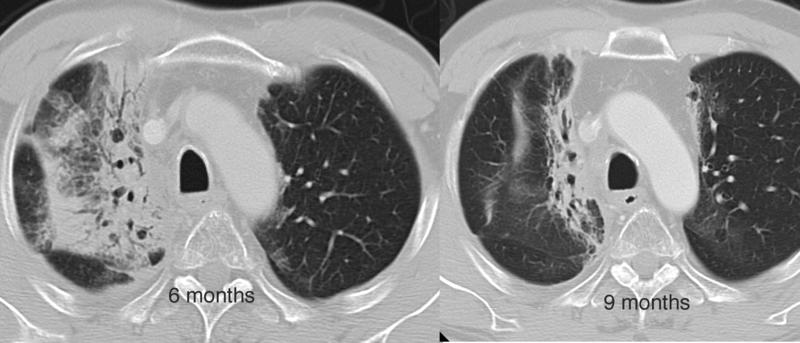

Gallery Pulmonary Fibrosis Radiation Radiation case 6

Radiation case 6